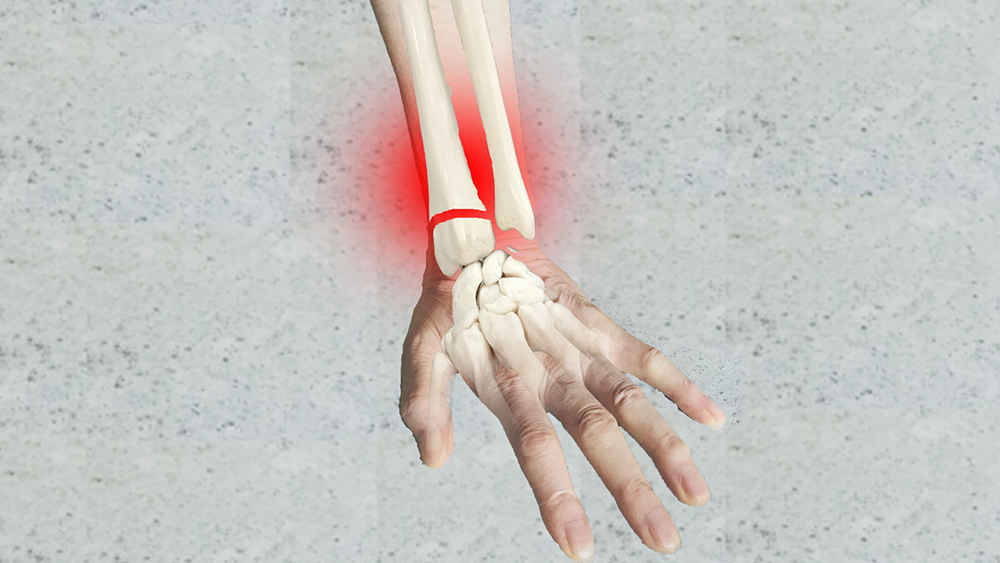

橈骨遠位端部骨折

橈骨は肘から手首にかけてある2本の骨のうち、親指側にある骨のことで、遠位端とは体幹から遠い場所、つまり手首を意味しています。

転倒した際に手をついた衝撃で手首の近くを発生する骨折です。

この骨折は高齢女性に多く見られますが、比較的若い人にも発生する場合があります。

治療には二通りあり、骨がずれていなければ保存療法が選ばれ、骨がずれている場合には手術療法が適応されることがあります。